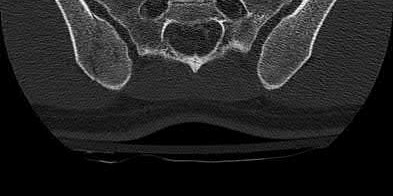

Which of the following images shows an injury pattern most consistent with a lateral compression type 3 pelvic ring injury?

Figure C is an axial CT scan of a lateral compression type 3 (LC3) pelvic ring injury.

Classically, LC3 injuries demonstrate an ipsilateral lateral compression and a contralateral APC (windswept pelvis) fracture pattern. The most common mechanism of injury in these cases is a rollover MVC or pedestrian vs. auto. LC1 injuries are characterized by an oblique or transverse ramus fracture and ipsilateral anterior sacral ala compression fracture, while LC2 injuries consist of a rami fracture and ipsilateral posterior ilium fracture dislocation (crescent fracture). While LC1 injuries can often initially be managed conservatively with protected weight-bearing and close observation, LC2 and LC3 pelvic ring injuries are almost universally operative.

Pennal et al. discuss a radiologic technique for assessing the forces producing pelvic disruption and its use in logically classifying pelvic injury. Based on this radiologic assessment and along with some biomechanical studies, they propose a classification system involving three major forces producing injury that can also be helpful in the management of these patients.

Young et al. performed a retrospective analysis of the plain radiographs of 142 cases of pelvic fractures and identified four patterns of force that presented with distinctive, recognizable radiographic appearances. They describe a classification system for pelvic fractures based on radiographic and clinical findings that correlates with associated injury to soft-tissue structures and enables the surgeon to begin corrective procedures rapidly.

Incorrect Answers:

Answer 1: This represents a lateral compression type 2 injury. Answer 2: This represents a lateral compression type 1 injury.

Answer 4: This represents an anterior posterior compression type 2 injury. Answer 5: This represents an anterior posterior compression type 3 injury.